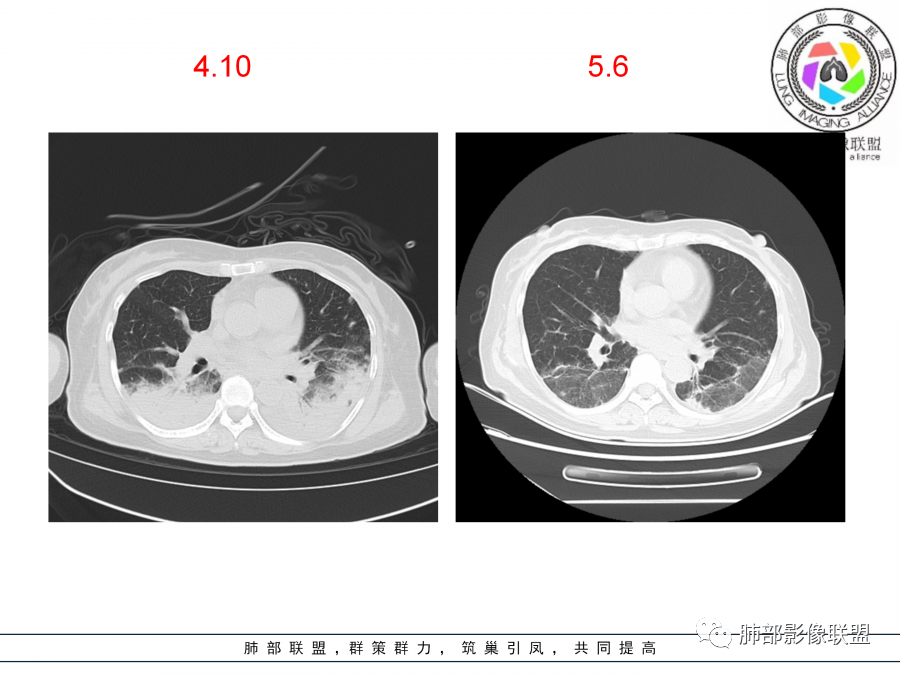

影像,第一次双肺中下叶胸膜下多发斑片状实变影,部分融合成,周围散发磨玻璃影,磨玻璃影内可见小叶间隔及小叶内间隔增厚,病变平行于胸膜,第二次间隔8天,双肺实变影明显进展,有重力作用,支气管近端堵塞,进展较快,临床有发热,血沉高,狼疮SLE阳性,考虑1:OP(机化性肺炎)2:SLE相关肺炎,建议支气管镜灌洗液病原学检测。

老年女性,咳嗽咳痰伴发热7天,白细胞不高,血沉快,降钙素原不高。其他化验未见明显异常,狼疮全套抗Ro/SSA阳性,双肺野靠近胸膜下磨玻璃实变影,支气管通畅,有充气征,沿胸膜下分布,有细网格征,7天后进展明显,实变影加重,胸膜肥厚,胸水不明显,心包少量积液?抗感染治疗无效,考虑非感染性疾病可能性大,结缔组织相关性肺病?狼疮性肺炎?机化性肺炎?鉴别病毒性肺炎。

第一次双肺中下叶胸膜下多发斑片状磨玻璃及实变影,病变平行于胸膜,支气管通畅,8天后,双肺实变影明显进展范围扩大,部分支气管近端堵塞,进展较快,胸腔积液,抗感染治疗无效,考虑:非感染性疾病:结缔组织相关性肺病。鉴别机化性肺炎。